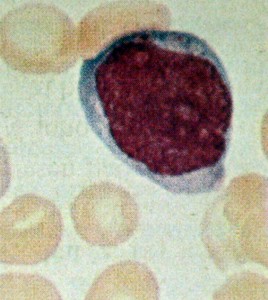

1.2 Promielócitos. Um grupo de células que consistem de diversos elementos que variam particularmente em sua relação núcleo- Citoplasma e em seus graus de granulação. Algumas características comuns dos promielócitos são a forma ovalada do núcleo, frequentes mente achatados ou recusados em um dos lados das células (em forma de rim); cromatina mediamente densa é reticulações heterogêneas. Os nucléolos são frequentemente visíveis. O citoplasma é azul-claro médio, com pequenas zonas e formas irregulares nas proximidades do núcleo, e contém grânulos azurófilos.

1.3 Promielócitos jovem: esse é o tipo de célula imatura mais frequente na granulopoiese. A forma mais velha ainda mostra uma estreita relação morfológica com o mieloblasto. Frequentes mente o núcleo contém nucléolos visíveis e o citoplasma mostra claramente alguns grânulos azurófilos. Com desenvolvimento completo do promielócito jovem é o maior das células da série granulocítica, devido ao aumento no tamanho do citoplasma que contém muitas granulações azurófilas. Ocasionalmente fragmentos plasmáticos com granulações típicas são visíveis.